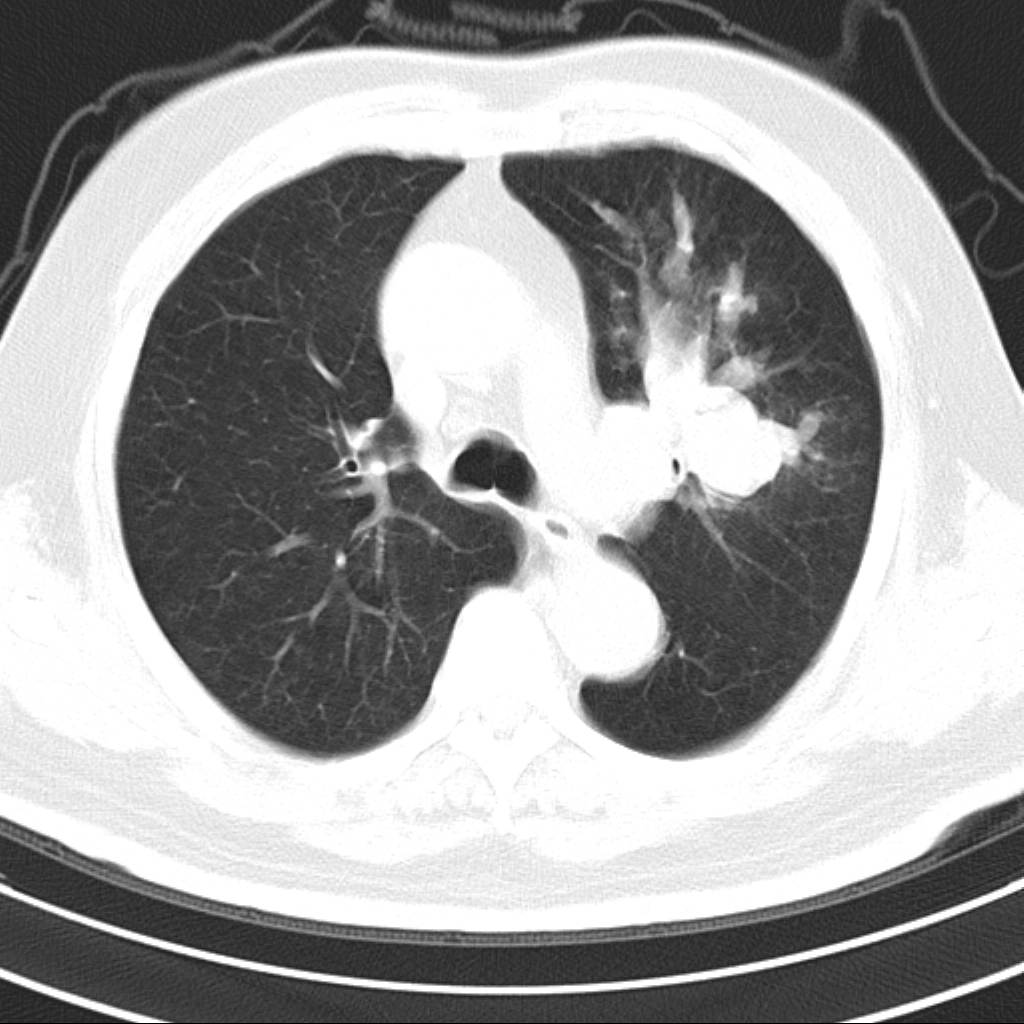

标题: CT18644:男,82岁,体检发现左肺阴影. [打印本页]

标题: CT18644:男,82岁,体检发现左肺阴影.

岁数太大,没有增强。麻烦见过的,给个诊断,顺便再说说病因

左侧中心型肺癌并粘液栓形成。很典型的。手套征。

支持 左肺上叶中央型肺癌并支气管内粘液栓形成。

尚不除外非感染炎症,过敏及哮喘曲霉菌病所致黏液栓塞,纸套征比较形象妾有一定特异性

考虑左肺上叶中央型肺癌并支气管内粘液栓形成。

支持 左肺上叶中央型肺癌并支气管内粘液栓形成,阻塞性肺炎

考虎左肺上叶中央型肺癌并支气管内黏液栓形成,不能增强是个遗憾,期待复查结果。